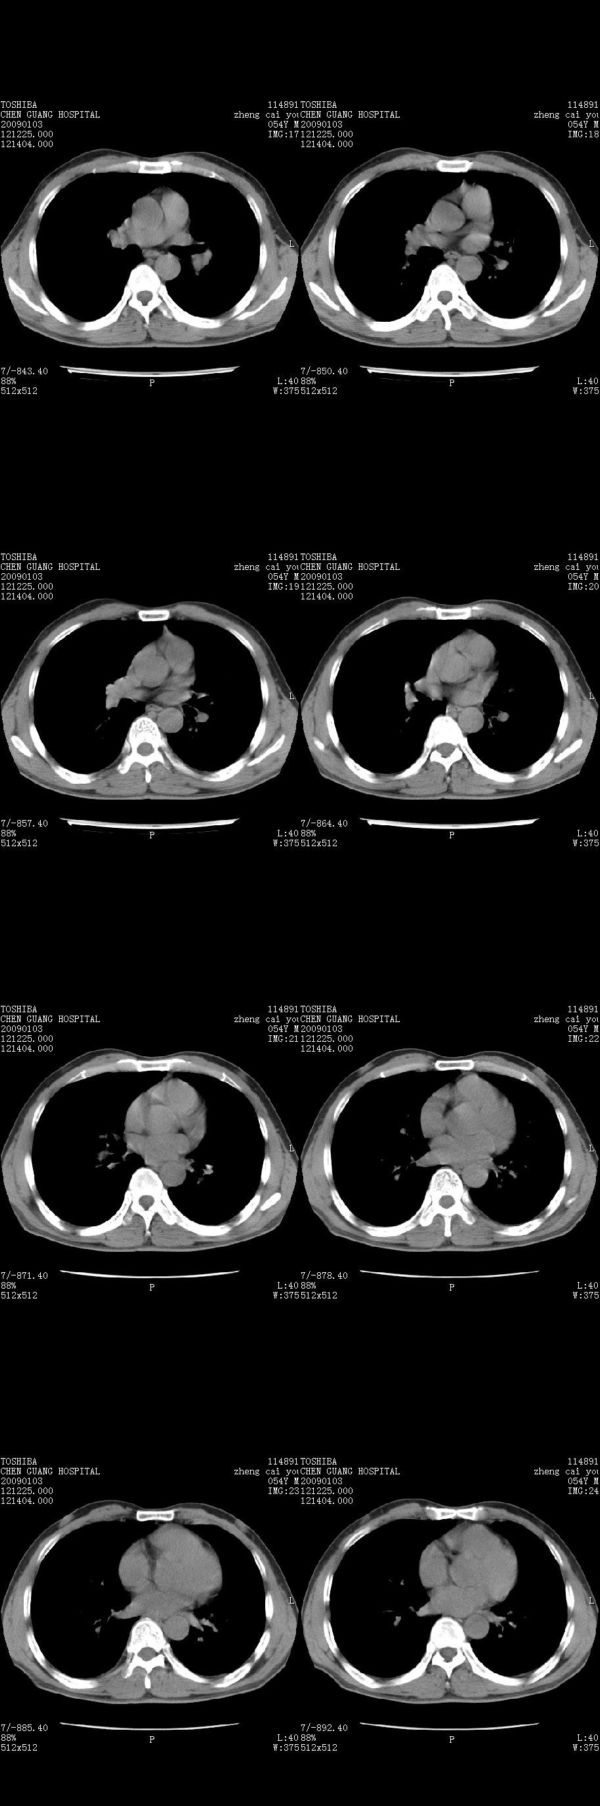

男,54岁,右侧胸部疼痛,平时吸烟,有抽烟后咳嗽咯痰史。昨天没把xiphoid软件吃懂,所以没把纵隔窗图像处理出来!请各位老师帮忙看一下右肺门有没有问题?谢谢!!!!!!!!!!

气管前腔静脉后似见增大淋巴结影,肺门区未见明显肿块影。肺窗示右肺中叶外侧段透亮度增高,可过一段时间再查一下对比一下,毕竟是自己的至亲,又有条件,辐射就顾不得了。

也觉得还好吧,只是右下肺动脉显粗了点,纵膈有钙化淋巴结,再有肺窗就更好了

各位老师:奇静脉增宽,肺上未见明显实变,这还需注意观察些什么?????

怎么不发点肺窗,胸痛原因很多,心、血管病变都可能,心、肺血管梗塞等,还包括功能性病变。

右侧肺门影增大,不除外增大淋巴结可能